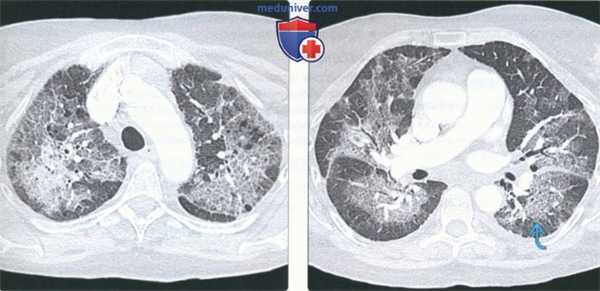

(Слева) На аксиальной КТВР у пациента с перибронхиальным интерстициальным фиброзом определяются двухсторонние асимметричные перибронховаскулярные участки снижения пневматизации в виде «матового стекла», центральные и периферические ретикулярные изменения. При наличии фиброза признаки структурных нарушений обычно выражены незначительно. В периферических отделах обоих легких визуализируются плохо отграниченные центрилобулярные очаги.

(Справа) На аксиальной КТВР у этого же пациента определяется утолщение стенок бронхов и перибронховаскулярные участки консолидации с симптомом «воздушной бронхографии».